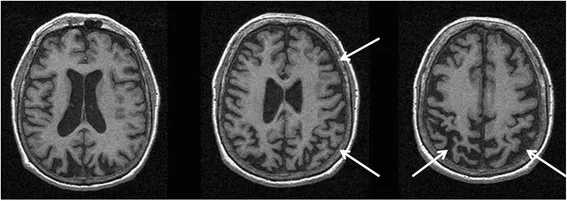

Corticobasal degeneration (CBD) is characterized by asymmetric limb apraxia ("alien limb"), rigidity, and dementia

Image credit: Usman Saeed et al., CC BY 4.0, via Wikimedia Commons

Parkinson's Plus Syndromes are syndromes that initially look like PD but have additional features. These syndromes include: <br><br>Progressive supranuclear palsy is characterized by gaze palsy, nuchal rigidity, early gait disorder, falls, and speech disorder<br><br>Dementia with Lewy bodies is characterized by early dementia, hallucinations, and cognitive fluctuations<br><br>Multiple system atrophy (MSA) is characterized by autonomic insufficiency, early incontinence, and cerebellar ataxia<br><br>Corticobasal degeneration (CBD) is characterized by asymmetric limb apraxia ("alien limb"), rigidity, and dementia<br><img src="a4fb8fd468dfcca151ca19fc3bb08416.webp"><br><i><span style="font-size: 10pt;">Image credit: <a href="https://commons.wikimedia.org/wiki/File:Corticobasal_degeneration_MRI.jpg">Usman Saeed et al.</a>, <a href="https://creativecommons.org/licenses/by/4.0">CC BY 4.0</a>, via Wikimedia Commons</span></i>